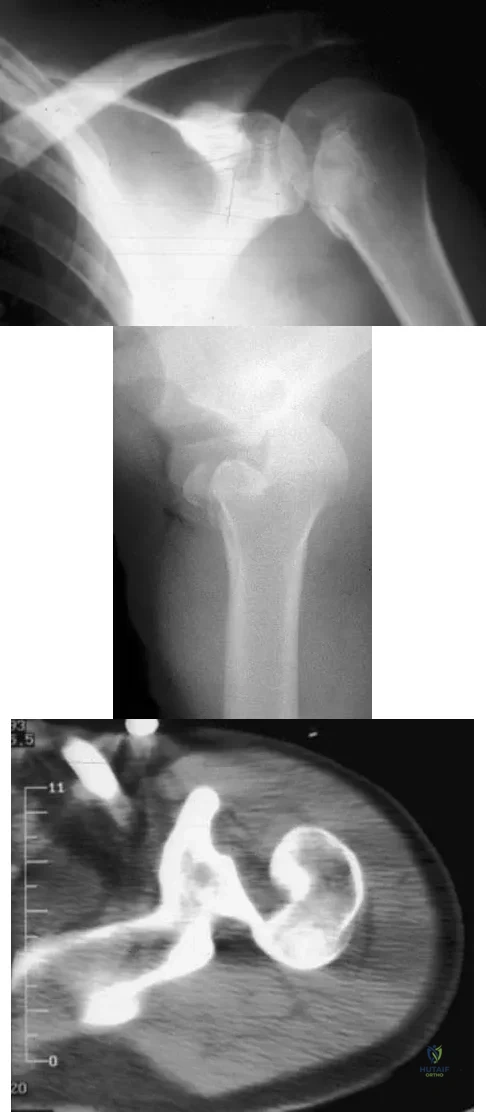

Question 47

A 21-year-old patient has had pain and a marked decrease in active and passive shoulder motion after having had a seizure 2 months ago as the result of alcohol abuse. Current AP and axillary radiographs and a CT scan are shown in Figures 26a through 26c. Management should consist of

Explanation